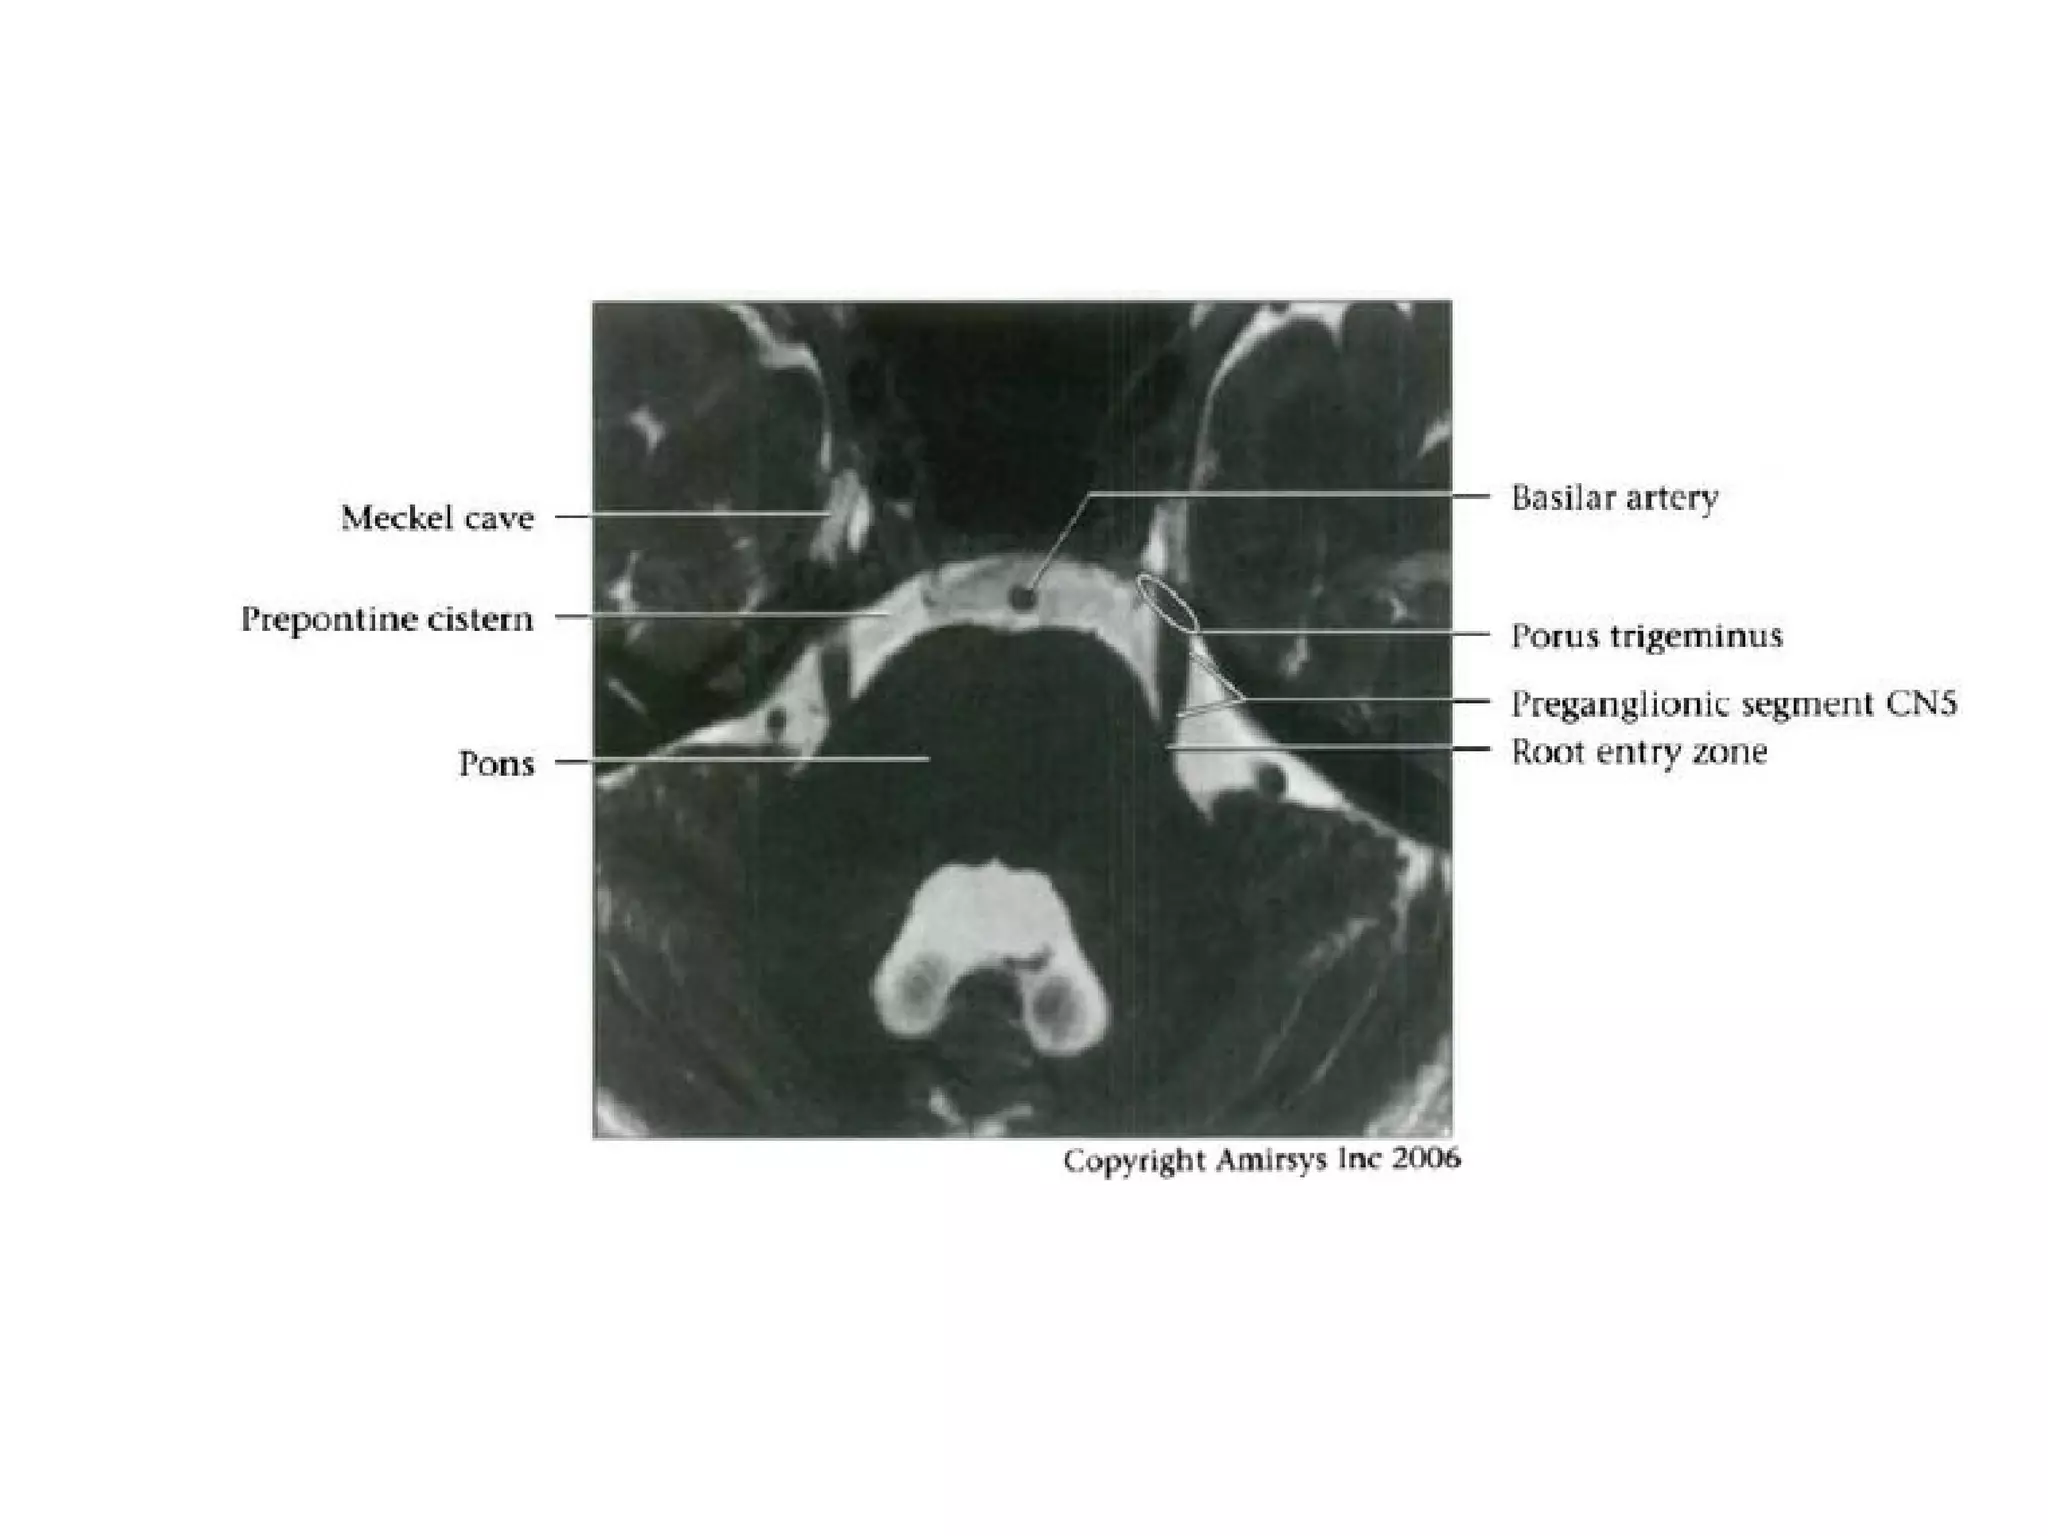

Trigeminal nerve.

Axial 0.8-mm-thick SSFP MR image shows the sensory

(arrowhead) and motor (large arrow) roots of the trigeminal

nerve

where they cross the prepontine cistern and enter the Meckel

cave (small arrows).

RadioGraphics 2009; 29:1045–1055

Cranial Nerve V:

The Trigeminal Nerve

• The trigeminal nerve is the largest cranial nerve.

• It is composed of a large sensory root that

runs medial to a smaller motor root.

• The roots emerge from the lateral midpons and

travel anteriorly through the prepontine cistern

and the porus trigeminus to the Meckel

(trigeminal) cave, a CSF-containing pouch in the

middle cranial fossa.